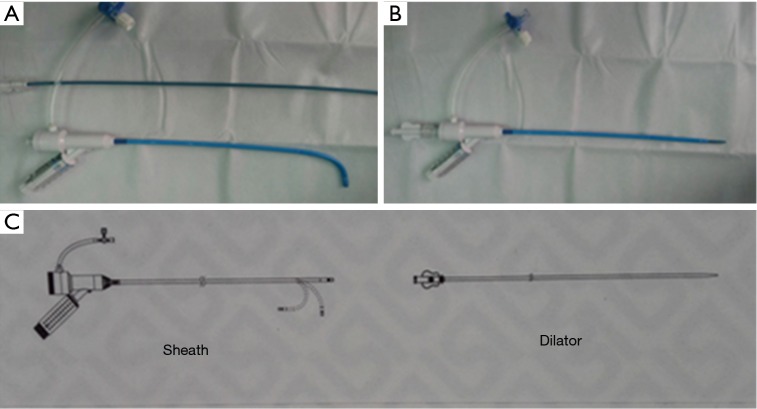

Figure 1.

(A) The curve-shape of the sheath with 90-degree angle; (B) the straight-shape of the sheath; (C) the sketch map of steerable introducer (FustarTM of Lifetech Scientific, Shenzhen).